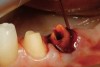

Figure 15  After removal of the defective restoration, it can be seen clinically that the margin of the preparation on the distal of tooth No. 21 was extremely subgingival. The surrounding periodontium was inflamed and hemorrhagic. The laser was used to perform apical repositioning of the bony crest using a closed-flap technique.

Figure 15